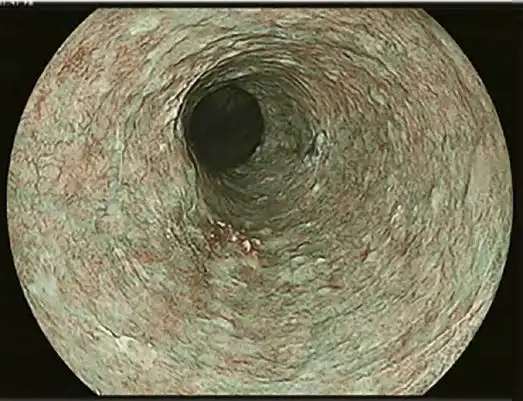

白光成像

内窥镜系统提供高清晰度和亮度的图像质量,以收集日常临床实践中诊断和治疗程序所需的视觉信息。